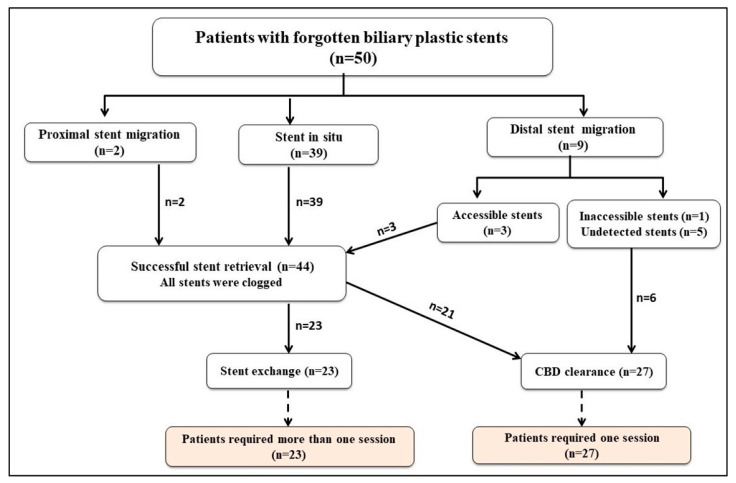

The flow chart revealed stent in situ (39 patients, 78%), distal stent migration (9 patients, 18%), and proximal stent migration (2 patients, 4%). Forty-four stents were retrieved (39 stents in situ, 3 accessible distally migrated stents, and 2 proximally migrated stents), and all of them were found to be clogged. Among these 44 patients, 23 patients had stent exchange, and 21 patients had CBD clearance. Furthermore, CBD clearance was achieved in the remaining 6 patients with distal stent migration (5 with undetected stents and 1 with an inaccessible stent) as illustrated in Figure 2.